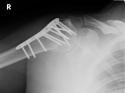

Bildbeschreibung: Metallversorgte Mittelhandfraktur